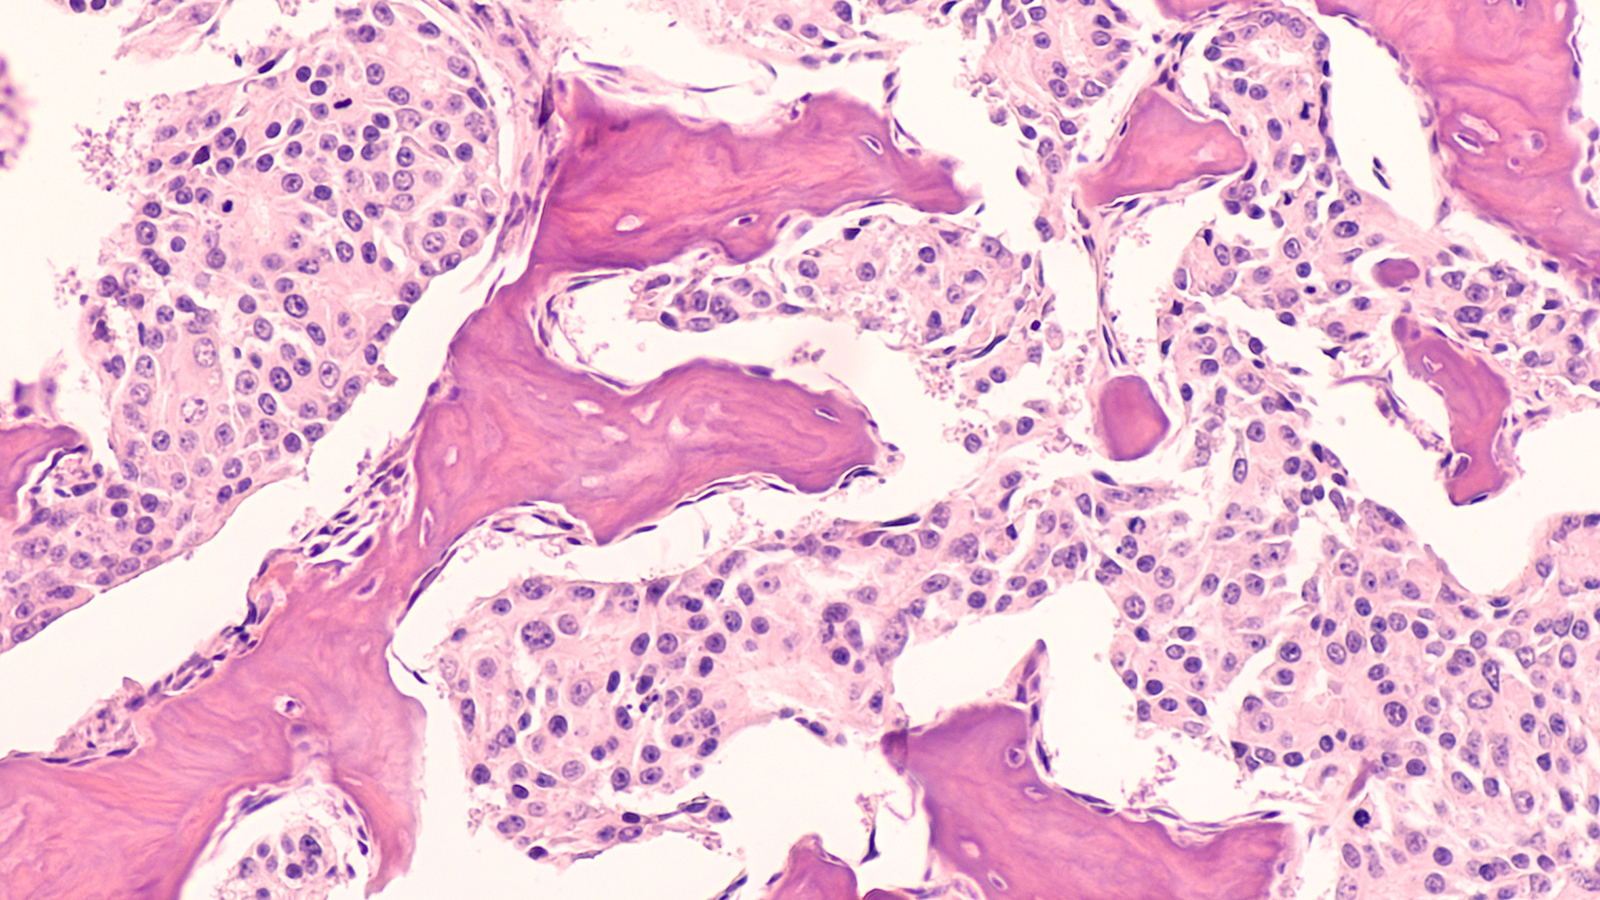

Cancer is not a uniform disease. Rather, cancer is a disease of phenotypic plasticity, meaning tumor cells can change from one form or function to another. This includes reverting to less mature states and losing their normal function, which can result in treatment resistance, or changing their cell type altogether, which facilitates metastasis.

Stochasticity in epigenetics is critical to how cancer evolves. For example, a condition called Barrett’s esophagus occurs when healthy cells in the esophagus develop features more like what cells lining the intestine normally have, which can ultimately lead to esophageal cancer. This is caused by progressive random changes in the epigenetic code, and this shift occurs more rapidly once it reaches a certain threshold. The stochastic nature of these epigenetic changes also leads to increased entropy in the function of those genes, and progression toward cancer.